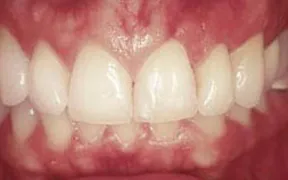

This is another case of a gummy smile. The gum tissue covered up too much of the teeth, which caused them to look short.

A crown lengthening procedure was performed, which evened the height of the gum tissue across the front teeth. This type of procedure typically leads to patients smiling with more confidence... and much more often!